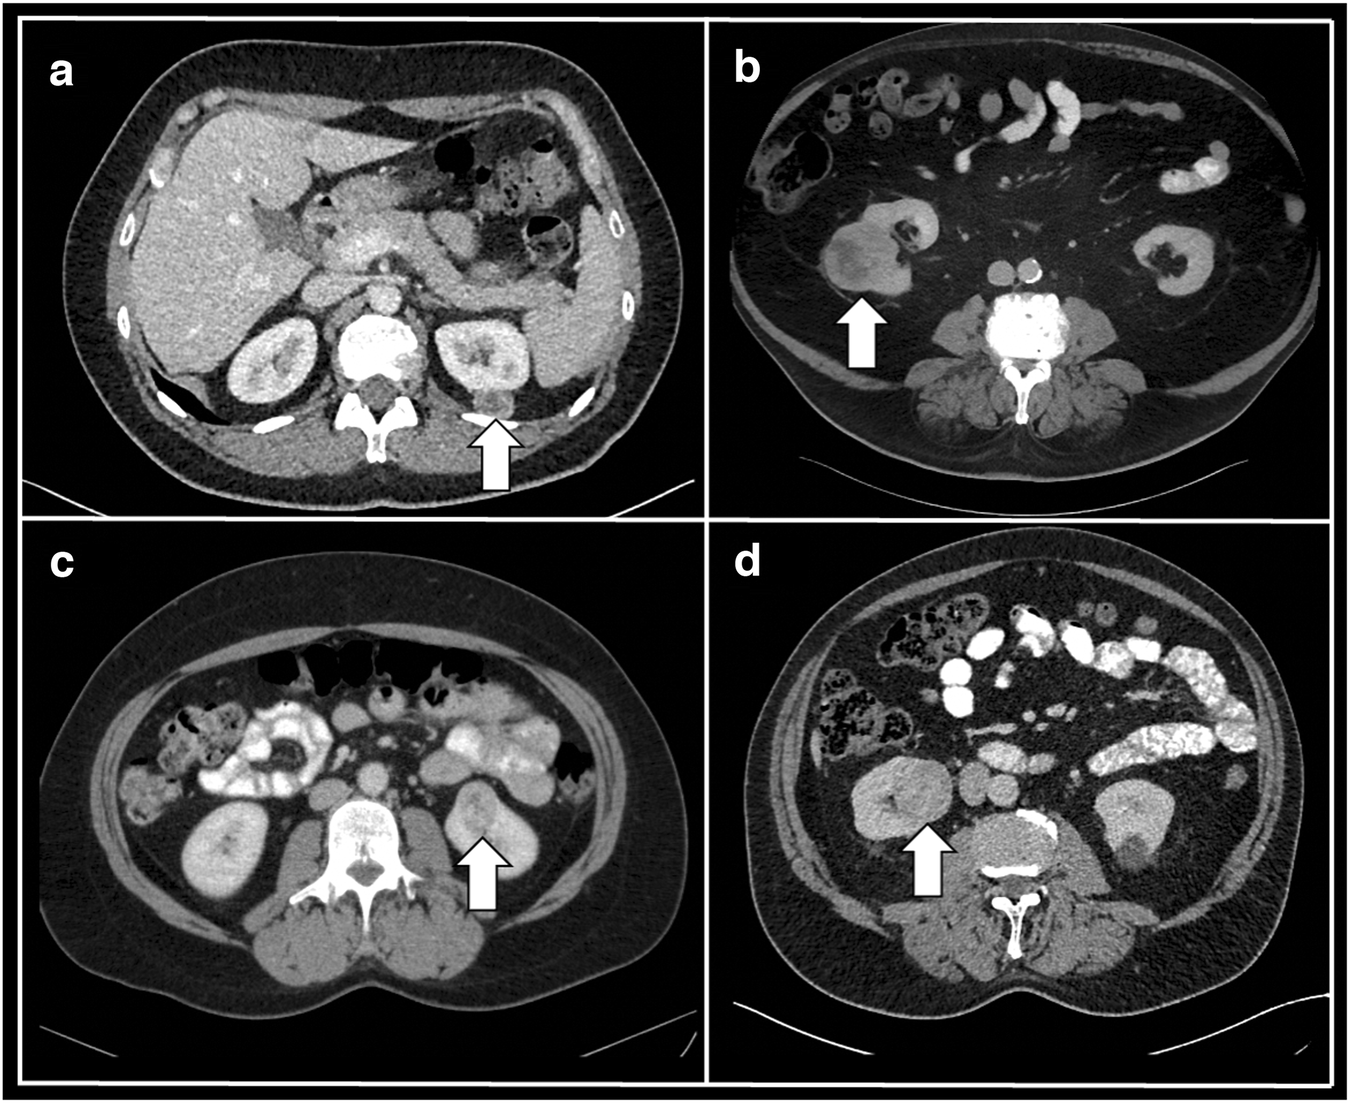

The mean 3-dimensional (3D) diameter of included renal tumors was 62 ± 36 mm in the training and 42 ± 16 mm in the testing dataset (p < 0.01). Representative patient cases are provided in Fig. 2.

Fig. 2

Representative CT case studies. a 49-year-old female patient with left-sided renal tumor (arrow), histologically identified as AML; b 70-year-old male patient with right-sided renal tumor (arrow), histologically identified as ccRCC; c 49-year-old female patient with left-sided renal tumor (arrow), histologically identified as oncocytoma; d 68-year-old male patient with right-sided renal tumor (arrow), histologically identified as pRCC